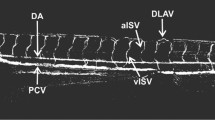

To unravel molecular changes of antiangiogenesis in developmental toxicity, we tested four reference compounds with known (SU4312, sorafenib) or putative antiangiogenic effect (methotrexate, rotenone). SU4312 is a selective inhibitor of the vascular endothelial growth factor receptor-2 (VEGFR2), a main regulator of angiogenesis (Sun et al. 1998). The pathway of VEGFR2 interaction and a causal link to the emergence of developmental defects were described in the adverse outcome pathway 43 (Knudsen et al. 2023). Sorafenib is a multikinase inhibitor targeting VEGFR2 among others (Wilhelm et al. 2006). Similar to SU4312, sorafenib is a pharmaceutical developed for cancer therapy via inhibition of angiogenesis (Wilhelm et al. 2004). In contrast to SU4312, sorafenib received marketing approval, and thus has been tested for developmental toxicity in the compulsory test species. An increased incidence in fetal malformations and retardations were observed in rats and rabbits (EMA 2007). Methotrexate is a folate antagonist and commonly known teratogen (Hyoun et al. 2012). The fetal methotrexate syndrome comprises a variety of congenital malformations observed in humans, ranging from microcephaly to cardiovascular anomalies and limb defects (Verberne et al. 2019). Several modes of action (MoAs) have been proposed to precede these malformations, including antiangiogenesis. It has been hypothesized that methotrexate exhibits antiangiogenic properties due to its efficacy in treating inflammatory diseases, which was supported by a rabbit cornea model showing a decrease in vascularization upon topical application (Joussen et al. 1999). Also, in zebrafish and human endothelial cells, an antiangiogenic phenotype has been observed upon methotrexate exposure (Schoors et al. 2015; Sun et al. 2009). In contrast, no significant reduction of microvessel outgrowth was observed in a human placenta assay (Fiehn et al. 2005), rendering the antiangiogenic potential of methotrexate as inconclusive. Similar to methotrexate, rotenone was connected to a multitude of MoAs. Given that rotenone is primarily a mitochondrial respiratory chain complex I inhibitor (Palmer et al. 1968), the mechanism of toxicity is strongly driven by impairments of the energy metabolism and oxidative stress. In vivo studies have found reduced fetal weight and skeletal abnormalities in rats (EPA 1987), while in vitro tests have classified rotenone as a putative vascular disruptor (McCollum et al. 2017). Thus, SU4312 and sorafenib have clearly been shown to interfere with angiogenesis, whereas the role of angiogenesis for developmental toxicity of methotrexate and rotenone is elusive.

Currently, developmental toxicity is mostly assessed using rats and rabbits. Yet, the zebrafish embryo (ZFE) has emerged as a promising alternative model and has shown to induce an antiangiogenic phenotype following exposure to SU4312 (Nöth et al. 2024), sorafenib (Beedie et al. 2016), methotrexate (Sun et al. 2009), and rotenone (McCollum et al. 2017). A major challenge with alternative models remains the extrapolation of findings to humans, as both exposure scenario and morphology differ between zebrafish and humans. Hence, recent alternative approaches incorporate the molecular mechanism of toxicity that precedes the apical morphological manifestation. These mechanisms are often congruent across species, as they rely on conserved signaling pathways such as those of early vertebrate embryogenesis (Artavanis-Tsakonas et al. 1999; NRC 2000; Zinski et al. 2018).